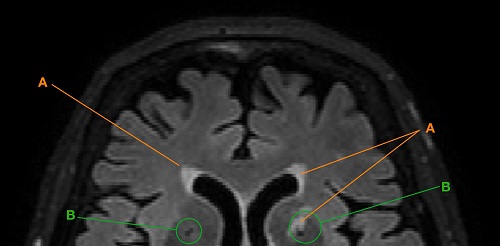

Akademische Ausbildung kann Hirnalterung günstig beeinflussen12. Januar 2022 Foto: ©AGPhotography – stock.adobe.com Eine gute Ausbildung und lebenslanges Lernen tragen auch im hohen Alter Früchte: Erste Befunde einer Langzeitstudie zeigen, dass bei Akademikerinnen und Akademikern gewisse Degenerationsprozesse im Gehirn weniger stark voranschreiten. Altersbedingte kognitive und neuronale Einschränkungen werden besser kompensiert. Eine gute Ausbildung gilt als sinnvolle Strategie, um beruflich erfolgreich zu sein und die eigene Persönlichkeit zu entfalten. Aber kann Bildung auch die Hirnalterung günstig beeinflussen? Dieser Frage ging ein Längsschnittprojekt des universitären Forschungsschwerpunkts “Dynamik des gesunden Alterns” unter der Leitung von Lutz Jäncke, Professor für Neuropsychologie an der Universität Zürich, nach. Das Forschungsteam begleitete über sieben Jahre mehr als 200 Seniorinnen und Senioren, die nicht dement, durchschnittlich bis überdurchschnittlich intelligent und sozial sehr aktiv sind. In regelmäßsigen Abständen wurden sie mittels Magnetresonanztomographie neuroanatomisch sowie neuropsychologisch untersucht. Anhand von aufwendigen statistischen Analysen konnte nun gezeigt werden, dass eine akademische Ausbildung eine geringere altersbedingte Hirndegeneration begünstigt. Hirnzerfall durch weiße Flecken oder schwarze Löcher Die Erstautorin Isabel Hotz vermaß im Rahmen ihrer Doktorarbeit mit teilweise neuen, automatisierten Methoden Lakunen und Hyperintensitäten der weißen Hirnsubstanz. Diese Degenerationsprozesse zeigten sich als “weiße Flecken” oder “schwarze Löcher” auf den digitalen Aufnahmen. Die Ursachen dafür sind nicht eindeutig bekannt und können in kleinen, nicht bemerkten Hirninfarkten, einer geringeren Durchblutung oder im Abbau von Nervenbahnen und -zellen liegen. In der Folge können Einschränkungen kognitiver Leistungen auftreten, vor allem dann, wenn dieser Zerfall an strategisch wichtigen Stellen des Gehirns auftritt. Ausschnitt eines mittels MRT gemessenen Gehirns im Horizontalschnitt mit Hyperintensitäten der weißen Substanz (A) und Lakunen (B). (Bild: UZH) Die Befunde zeigen, dass Seniorinnen und Senioren mit einer akademischen Ausbildung im Verlauf der sieben Jahre eine deutlich geringere Zunahme dieser typischen Hirndegenerationszeichen aufweisen. “Darüber hinaus waren Akademikerinnen und Akademiker auch in der Verarbeitungsgeschwindigkeit schneller und genauer – zum Beispiel beim Vergleich von Buchstaben, Zahlen oder Mustern. Sie offenbarten insgesamt eine geringere Leistungsabnahme in diesem wichtigen psychischen Verarbeitungsprozess”, fasst Hotz zusammen. Reserven werden angezapft Damit ergänzen diese Befunde erste Hinweise anderer Forschungsgruppen, dass Bildung einen günstigen Einfluss auf die Hirnalterung hat. Frühere Studien zeigten zudem, dass die Verarbeitungsgeschwindigkeit von der Integrität der im Hirn verteilter neuronaler Netzwerke abhängt. Werden diese in Mitleidenschaft gezogen, sinkt die Verarbeitungsgeschwindigkeit. Auch wenn noch kein kausaler Mechanismus zwischen Bildung und geringerer natürlicher Hirndegeneration gefunden wurde, liegt zumindest ein Zusammenhang nah: “Wir vermuten, dass eine gute Ausbildung im Laufe des Lebens zu einer Zunahme der neuronalen und kognitiven Netzwerke führt und damit Reserven aufbaut. Im Alter können dann eintretende Hirnbeeinträchtigungen besser kompensiert werden”, sagt Neuropsychologe Jäncke. Möglich sei auch, dass ein Gehirn, das bis ins hohe Alter geistig rege bleibt, weniger anfällig für Degenerationsprozesse ist. Dies müsse allerdings im weiteren Verlauf der noch andauernden Längsschnittstudie überprüft werden, so der Forscher.